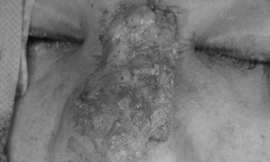

TPO - Đến bệnh viện thăm khám trong tình trạng biến dạng vùng mặt, nữ bệnh nhân cho biết trước đó đã tiêm chất làm đầy filler để nâng mũi. Các bác sĩ xác định người bệnh đã hoại tử da, nguy cơ để lại sẹo sau điều trị.

Hiện nay, nhiều người vẫn chưa thật sự hiểu việc tiêm chất làm đầy dỏm, không rõ nguồn gốc cũng giống như tiêm ung thư vào người. Chị T.H.C, 38 tuổi, ngụ tại Vũng Tàu đã phải gánh chịu chịu hậu quả sau khi nâng mũi bằng cách tiêm chất làm đầy không rõ nguồn gốc.